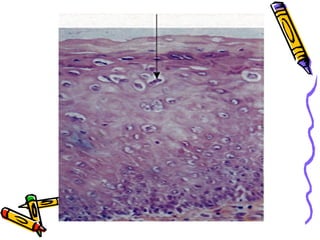

This document discusses benign and malignant diseases of the vulva. It begins by outlining common symptoms of vulvar diseases such as itching, burning, and bleeding. It then provides an overview of the general pathology and terminology used to describe vulvar diseases. The document categorizes vulvar lesions as white, red, or brown/bluish and discusses specific conditions that present with each color, including vitiligo, lichen sclerosis, squamous cell hyperplasia, infections, dermatitis, and various precancers and cancers. Treatment options are provided for some conditions like HPV. Throughout, it emphasizes the importance of inspection, palpation, biopsy prior to treatment, and using medical therapy for benign lesions.